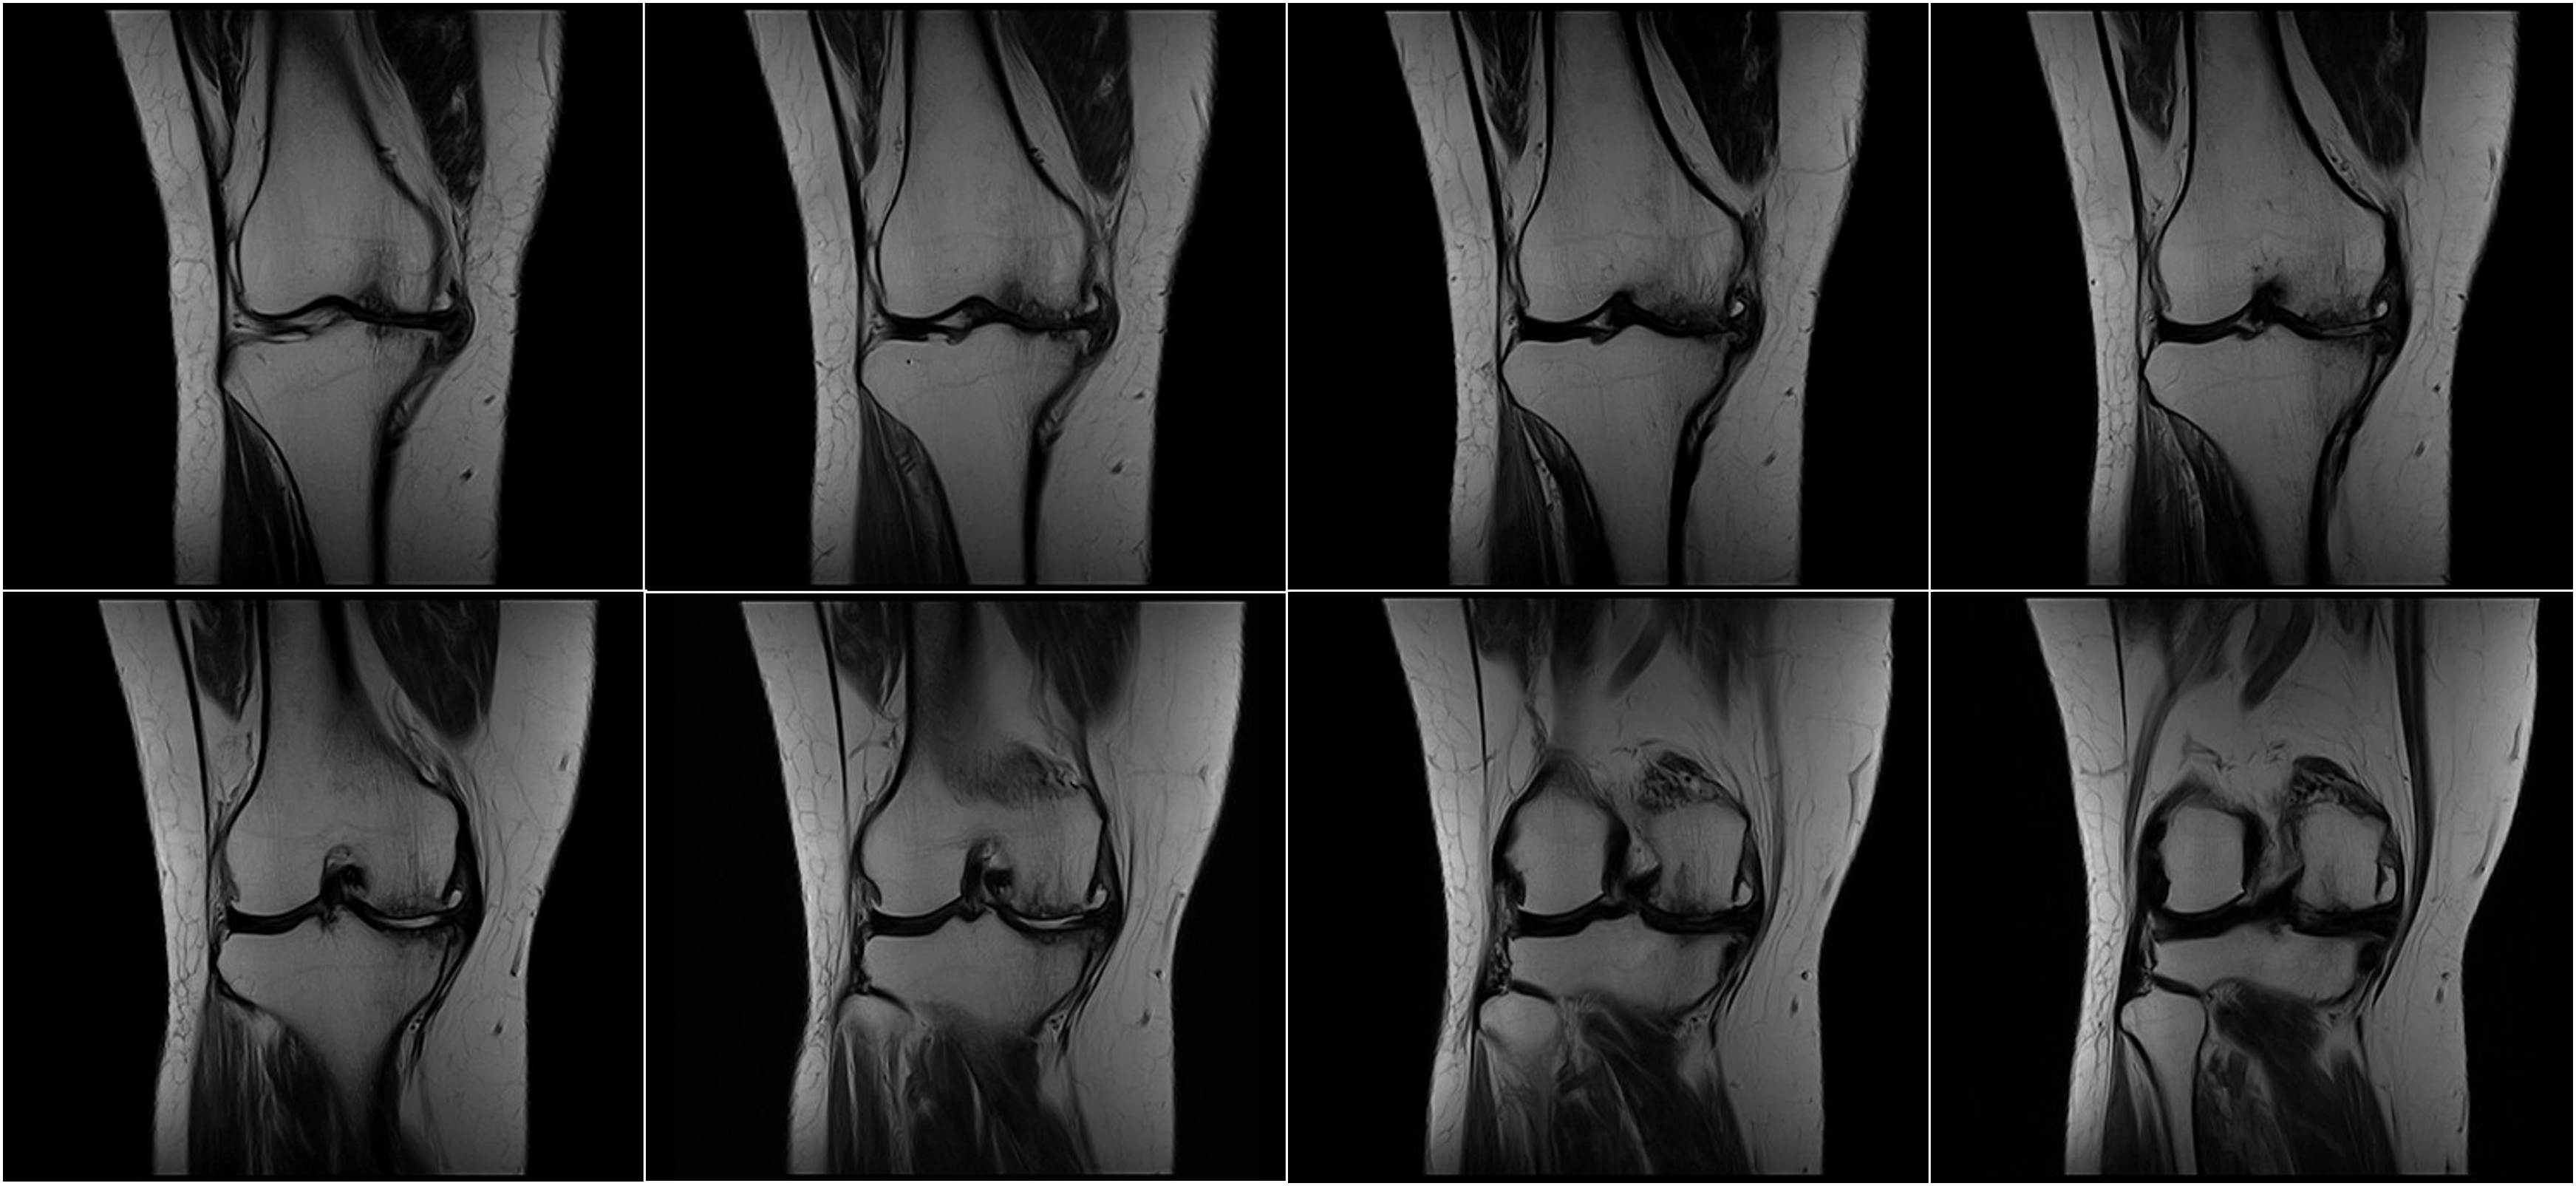

Hình ảnh lâm sàng